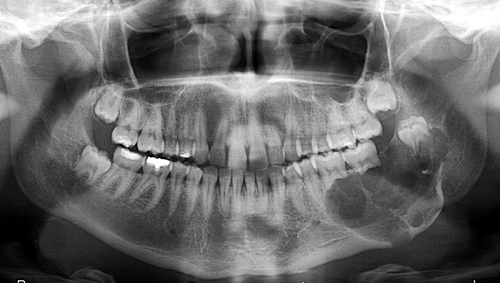

Odontogenik kistlər çənədə ən çox rast gəlinən törəmələrdən olub, başlanğıcını diş orqanından götürür. Bu törəmələr epitel hüceyrə qatı ilə döşənmiş zarla əhatə olunmuş, daxilində isə spesifik maye yerləşən kisəni xatırladırlar. Odontogenik kistlər ya xroniki iltihab nəticəsində ya da inkşaf anomaliyası nəticəsində yarana bilir.

İnkşafı və böyüməsi tədricən baş verdiyindən, bu proses pasiyent tərəfindən demək olar ki hiss edilmir. Yalnız törəmənin ciddi ölçülərə çatması nəticəsində və ya iltihablanması nəticəsində meydana çıxan kliniki əlamətlər nəticəsində aşkarlanır. Əksər hallarda isə çəkilən diş və çənə rentgen şəkillərində təsadüfən rast gəlinir.